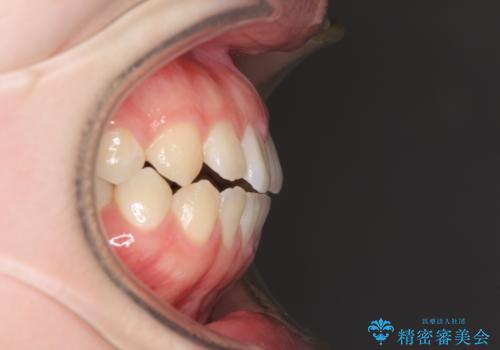

非抜歯で口元の突出感を少し改善させる治療も提案しましたが、最大限口元を引っ込めたいとのことでした。

上下左右第一小臼歯4本を抜歯し、ワイヤー装置により矯正治療を行うこととしました。

装置除去後には、スッキリとした口元となり、大変満足していただきました。